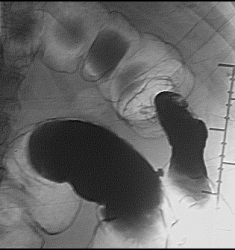

Ну "перво - наперво" шикарно видно "сужение"

Это исследование я проводил сегодня утром, помимо данного участка с "органикой" есть ещё один участок, который отчётливо видно на МСКТ при анализе изображений, но почему то мой более старший коллега ни стал об этом указывать ссылаясь на то, что преригатива скопического и эндоскопического исследований, у нас там конечно ни шуточная баталия разгорелась, и вообще поставил данный участой симметричного сужения подвопросом:

Именно этим мне и показался данный случай интересным, получается именно данный участок видели эндоскописты, а это участок поперечного отдела ободочной кишки, даже почти селезёночный угол, чётко видно на МСКТ. И получается что первично-множественный рак толстого кишечника, если я не прав поправте меня.

А в нисходящий и сигме, на фоне газа - это полипы?

Множественный дивертикулёз сигмовидного, нисходящего и поперечного отделов ободочной кишки.

А вот, по поводу, наличия дивертикулёза у меня весьма больние сомнения.

То что в нисходящем отделе ободочной кишки-дивертикулез это на 100%, по поводу "сигмы" ещё можно посомниваться, но этот участок попадает под резекцию, у морфологов узнаю, а вот ампула прямой кишки, это да, что как то я сомневаюсь до сих пор что это остаточные каловые массы, пациент подготовлен-отлично, возможно полип, но как бы ещё хуже не оказалось, но в дальнейшем всё равно попадёт к нам на контроль, плюс эндоскописты. Кстати вроде планы ещё резко сменились по ведению этого пациента, думаю хирурги озадачились, хотя трансфузиолог свои запеси уже оставил.